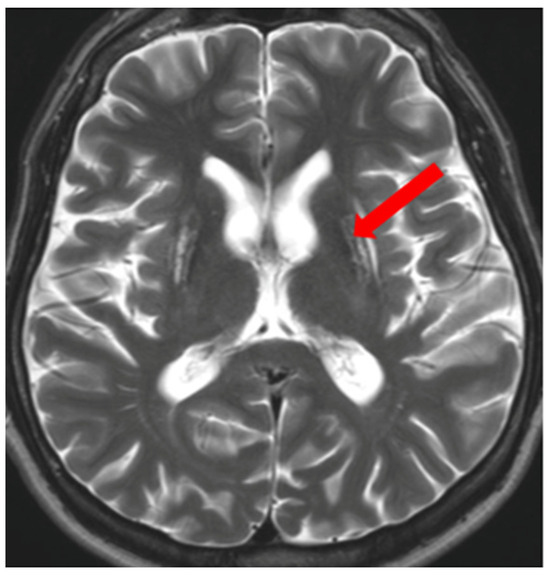

- Rędzia-Ogrodnik, B.; Członkowska, A.; Antos, A.; Bembenek, J.; Kurkowska-Jastrzębska, I.; Przybyłkowski, A.; Skowrońska, M.; Smoliński, Ł.; Litwin, T. Pathognomonic neuroradiological signs in Wilson’s disease—Truth or myth? Park. Relat. Disord. 2023, 107, 105247. [Google Scholar] [CrossRef] [PubMed]

- Hitoshi, S.; Iwata, M.; Yoshikawa, K. Mid-brain pathology of Wilson’s disease: MRI analysis of three cases. J. Neurol. Neurosurg. Psychiatry 1991, 54, 624–626. [Google Scholar] [CrossRef] [PubMed]

- George, U.; Varte, N.; Rathore, S.; Jain, V.; Goyal, S. “Split thalamus”: Internal medullary involvement in Wilson’s disease. Neurol. India 2010, 58, 680. [Google Scholar] [CrossRef] [PubMed]

- Sener, R.N. The claustrum on MRI: Normal anatomy, and the bright claustrum as a new sign in Wilson’s disease. Pediatr. Radiol. 1993, 23, 594–596. [Google Scholar] [CrossRef] [PubMed]